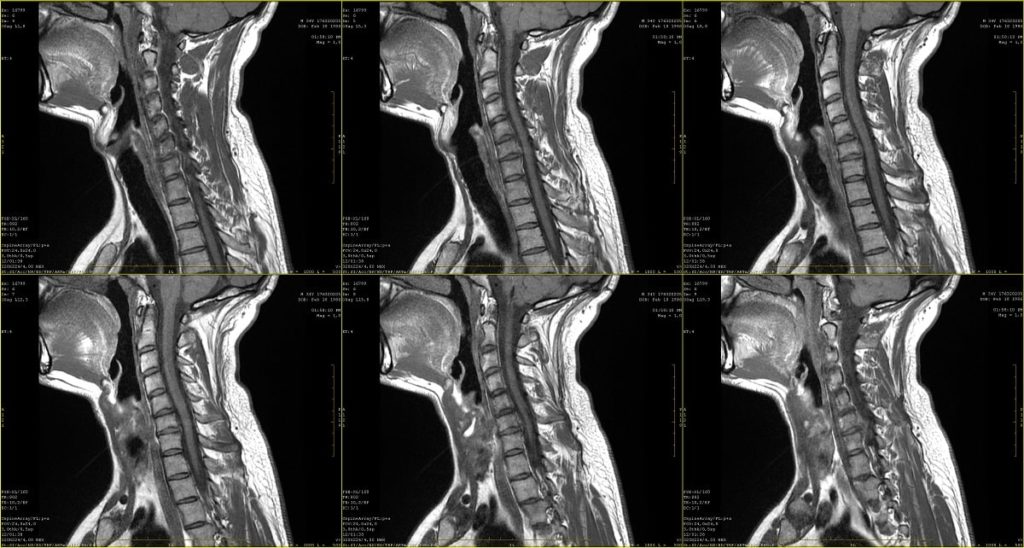

Finalmente, en esta imagen se muestran 6 resonancias magnéticas con un plano sagital del área del cuello: